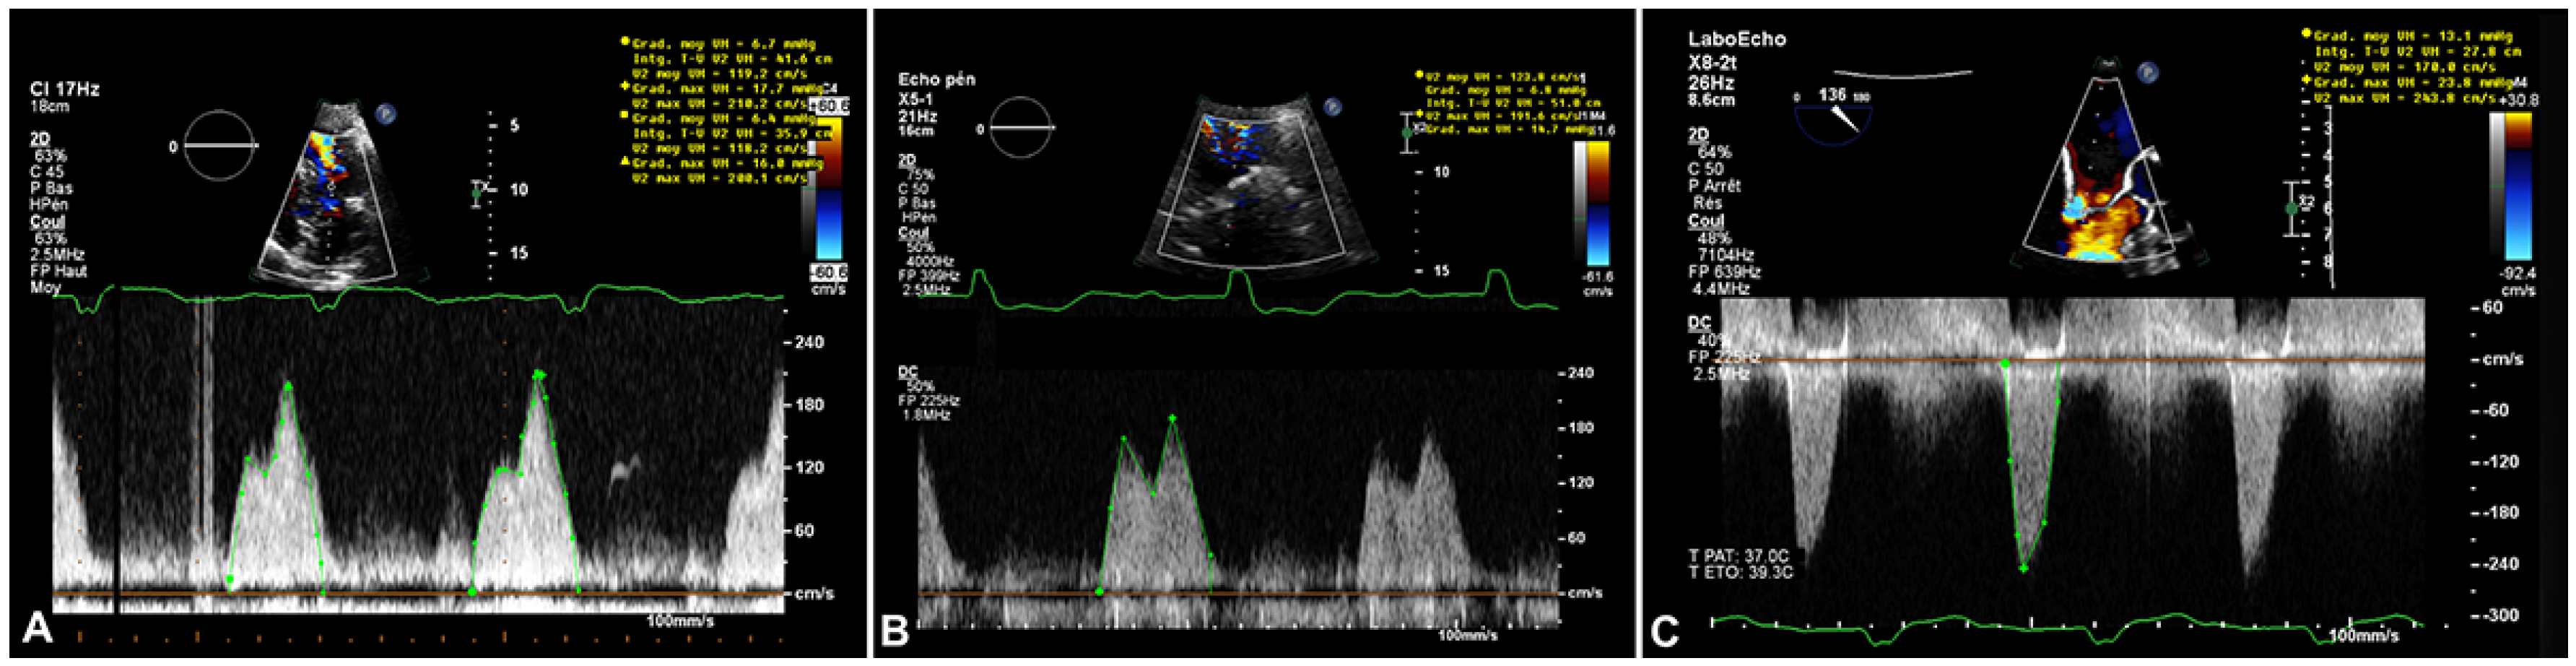

In the emergency department the patient’s vital signs (oxygen saturation 88%), clinical examination (tachypnoea, orthopnoea, bilateral lung crackles), laboratory tests (elevated N-terminal pro-B-type natriuretic peptide [NT-proBNP]) and chest X-ray (lung congestion) confirmed the diagnosis of acute heart failure, albeit of unclear aetiology: her blood pressure was only mildly increased, mild troponin elevation argued against an acute coronary syndrome, haemoglobin levels and heart rate were stable (Table 1). The patient was admitted for oxygen supplementation and intravenous diuretics with rapid recovery ensuing in a few days. A TTE documented normal heart function but an increase in the size of the cardiac mass ( 46 mm × 31 mm compared with 36 mm × 27 mm 4 years before), the mean gradient across the mitral valve was unchanged at 6–7 mm Hg at a heart rate of 65 bpm (Figure 2) The mitral valve area obtained by two-dimensional planimetry from the parasternal short axis view was 1.2 cm2 (Figure 3B). No other significant valve disease was found. Transoesophageal echocardiography (TOE) showed moderate mitral stenosis. The mitral valve orifice measured by three-dimensional planimetry was 1.4 cm2 (Figure 3A). Remarkably, there was an increase in the mean diastolic mitral gradient from 6 mm Hg at the time of the TTE to 13 mm Hg on TOE, probably due to a higher heart rate of 85 bpm (Figure 5). A CT scan showed an increased size of the mass (Figure 4). Due to the frailty of the patient and in accordance with her wish not to undergo any invasive treatment, surgery was not proposed. The patient was discharged before being admitted 2 months later for another episode of acute heart failure treated with intravenous diuretics. The therapeutic attitude was altered and at this time the patient was again discharged for ambulatory follow up for treatment adjustment and only symptomatic management if acute heart failure happens again.

Figure 5. A. Transthoracic echocardiogram (TTE), continuous Doppler transmitral mean gradient (6 mm Hg at 80 bpm) on initial presentation in 2016 B. TTE, continuous Doppler transmitral mean gradient (6–7 mm Hg at 65 bpm) 4years later in 2020. C. Transoesophageal echocardiogram, continuous Doppler transmitral mean gradient (6–13 mm Hg at 85 bpm) in 2020.